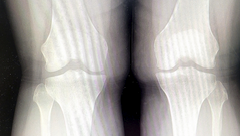

무릎 연골 주사 가격 무릎 연골 통증 원인 관리방법 등 무릎 연골에 관한 정보 알아보도록 하겠습니다. 무릎 연골 재생 주사는 퇴행성 관절염이나 스포츠 부상 등으로 인해 손상된 무릎 연골을 보호하고 회복시키기 위한 치료법입니다. 연골은 뼈와 뼈 사이에 있는 부드러운 조직으로, 관절의 움직임을 원활하게 하고 충격을 흡수하는 역할을 합니다. 하지만 연골은 한번 닳거나 손상되면 자연적으로 재생되지 않기 때문에, 통증이나 염증, 관절의 변형 등의 증상이 발생할 수 있습니다.

무릎 연골은 무릎 관절의 뼈 사이에 있는 부드러운 조직으로, 뼈가 서로 마찰하는 것을 방지하고 충격을 흡수하는 역할을 합니다. 무릎 연골이 손상되거나 마모되면 무릎 통증이 발생할 수 있습니다. 무릎 연골 통증의 원인은 다양하지만, 여기서는 가장 흔한 3가지 원인에 대해 알아보겠습니다.